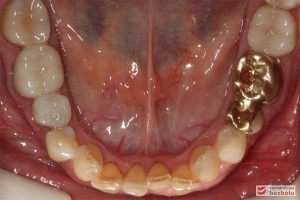

Do naszej placówki zgłosiła się starannie planująca swoje działania Europejka, mieszkająca na stałe w Kotlinie Jeleniogórskiej. Jej oczekiwania dotyczyły bardzo metodycznie zaplanowanego planu leczenia. Celem jaki postawiła przed naszym zespołem lekarzy było wyeliminowanie wszystkich wątpliwych i nierokujących wypełnień, a także poprawa estetyki w zakresie lewego siekacza centralnego w szczęce. Został rozpisany blisko dwuletni plan wymiany zużytych i nieszczelnych wypełnień amalgamatowych i kompozytowych. Zaplanowano również przygotowanie endodontyczne wybranych zębów w szczęce i żuchwie, a także zaopatrzenie w inlay’e porcelanowe i korony ceramiczne wykonane w systemie e-max.